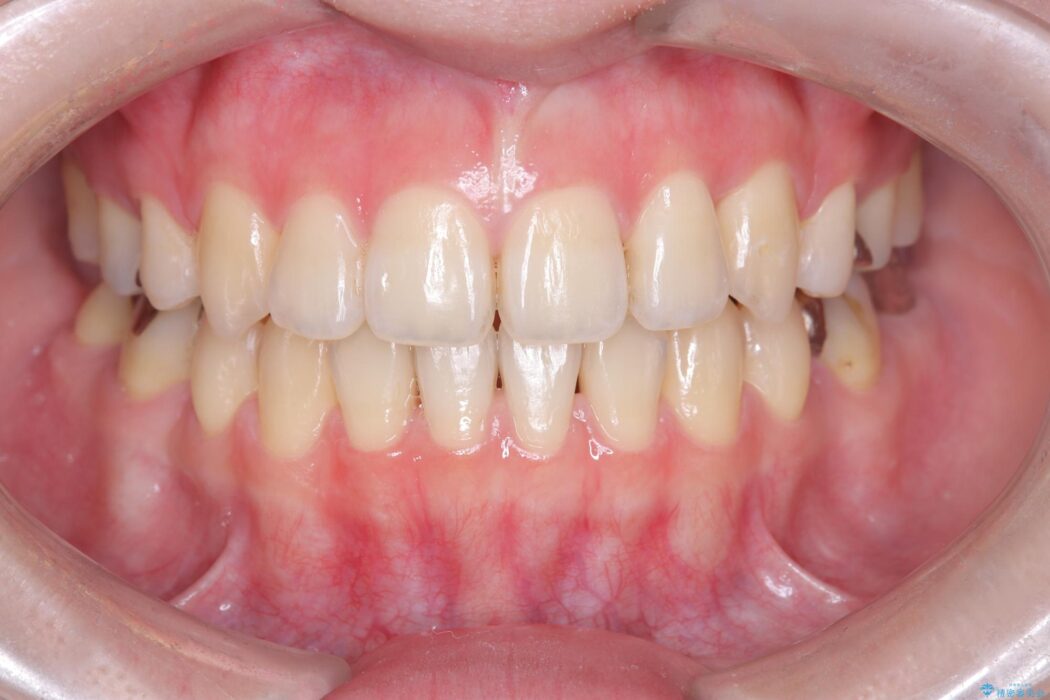

気になっていたガタつきや開咬が改善され、見た目だけでなく咬み合わせの機能面も大きく向上し、大変ご満足いただけました。

また、治療期間も比較的短期間で終了することができました。